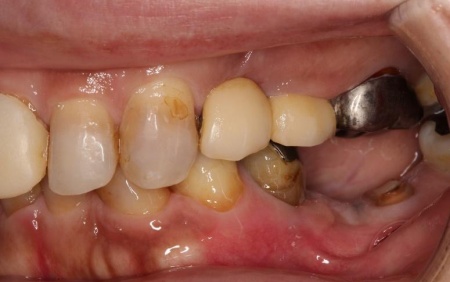

治療前

拝見したところ、もともと左上の歯と左下前歯が欠損しているうえ、奥歯の欠損も進んでいたため、噛み合わせが低くなっていました。

奥歯が噛み合わない状態になったことで、上前歯が前方に押し出され、出っ歯のようになっています。

また、下の歯は歯根だけが残る「残根」もあり、全体的に噛み合わせが不安定です。

さらに食いしばりの習慣があることから、残っている歯や顎関節に過度な負荷がかかっていると考えられます。

このまま放置すると、食いしばりによる歯の破折や欠損の増加、顎関節への負担増大、前歯の突出の進行などのリスクがあるため、早急に治療を開始する必要があると診断しました。

「20代のころから、痛いときだけ歯科医院に通っていた。歯が折れたり抜けたりしたため、複数の歯をつなげた被せ物を装着しているが、噛みにくくなってしまった。また、最近は食いしばりもあり奥歯が痛む。複数の歯科医院で矯正治療を断られたので、解決策が見つからずに困っている」とご相談いただきました。